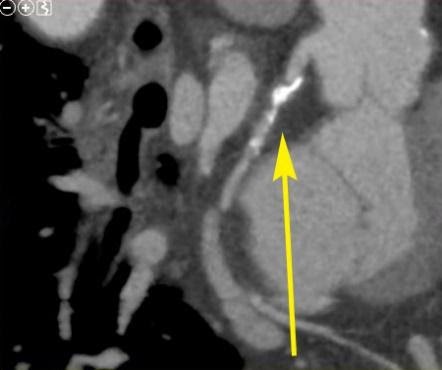

The CREDENCE Trial demonstrated that CT scanning can measure the significance of heart artery blockages as well as, if not better than, stress testing.

Dr. Clay Chappell performs a cardiac catheterization procedure at St. Mary's, using balloon angioplasty and medicated stent implantation to reopen a blocked artery in the patient's heart.